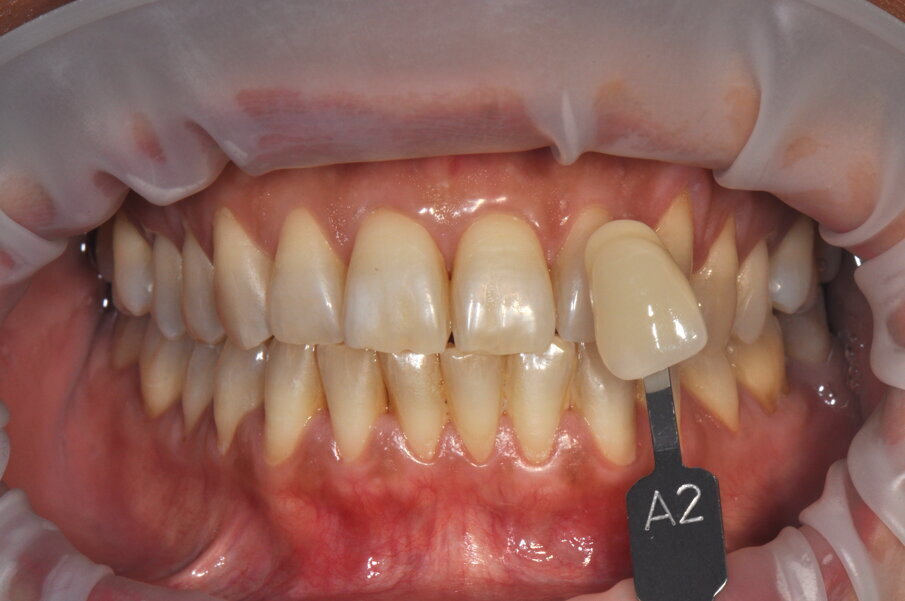

Fig. 6 - Fotografia frontale scattata prima della seduta di igiene orale professionale (Guided Biofilm Therapy).

Fig. 8 - Rilevamento del colore a tempo zero utilizzando la scala “Vita” D3.